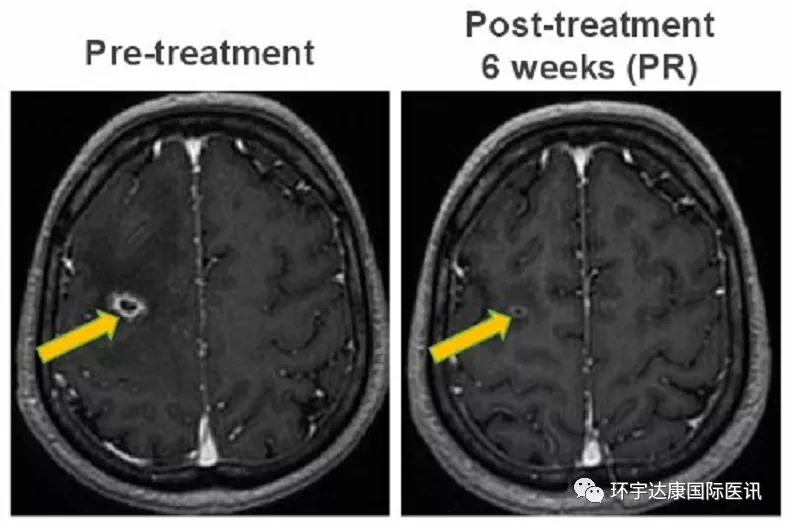

NO.1、强效抗脑转

一位49岁的男性患者,确诊为ROS1阳性非小细胞肺癌,既往接受了化疗和克唑替尼的治疗后病情进展,出现脑转移。接受Taletrectinib(600mg,QD)治疗后迅速出现响应,第6周的影像学检查显示脑部转移病灶明显缩小,达到部分缓解状态(PR)。